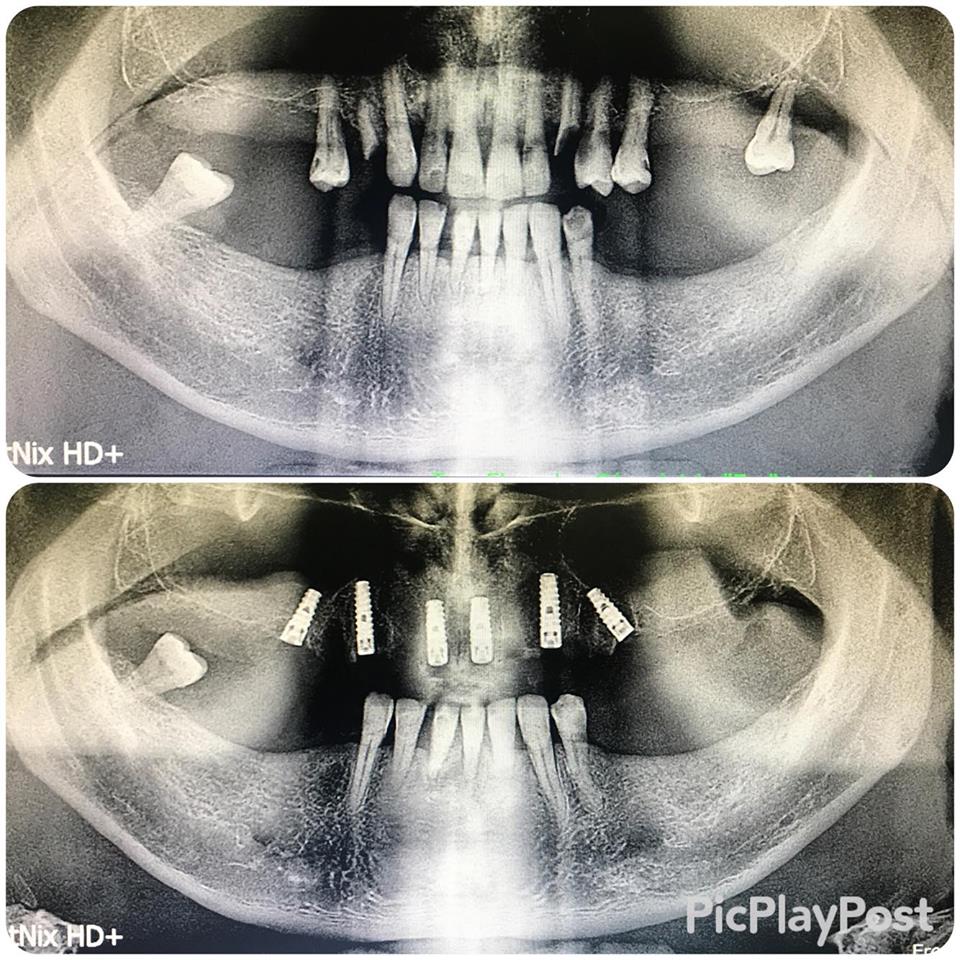

İMPLANT TEDAVİSİ

implant tedavisi